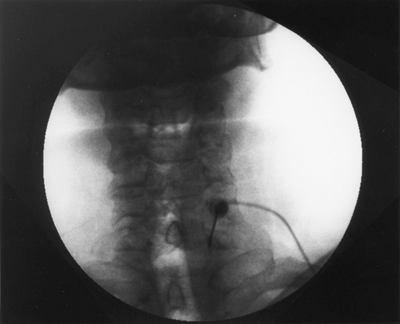

process and the C7 vertebral body (Fig. 63-2). Use 2 mL of Isovue-200 (Bracco Diagnostics, Princeton, NJ) for verification of needle position. Figure 63-3 presents an anteroposterior (A) and lateral view (B).

Figure 63-3. A: Anteroposterior view. B: Lateral view.